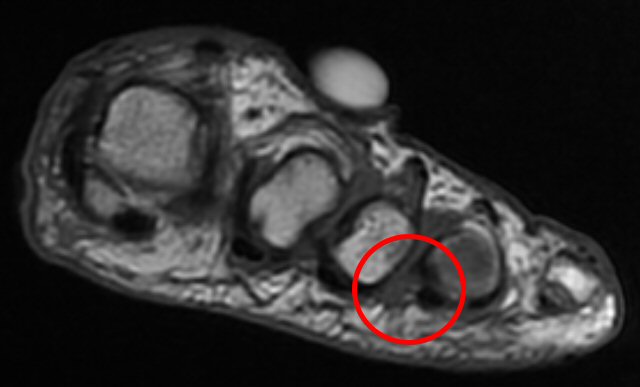

T1-viktad MR-bild med mortons neurom mellan metatarsaler 3 och 4